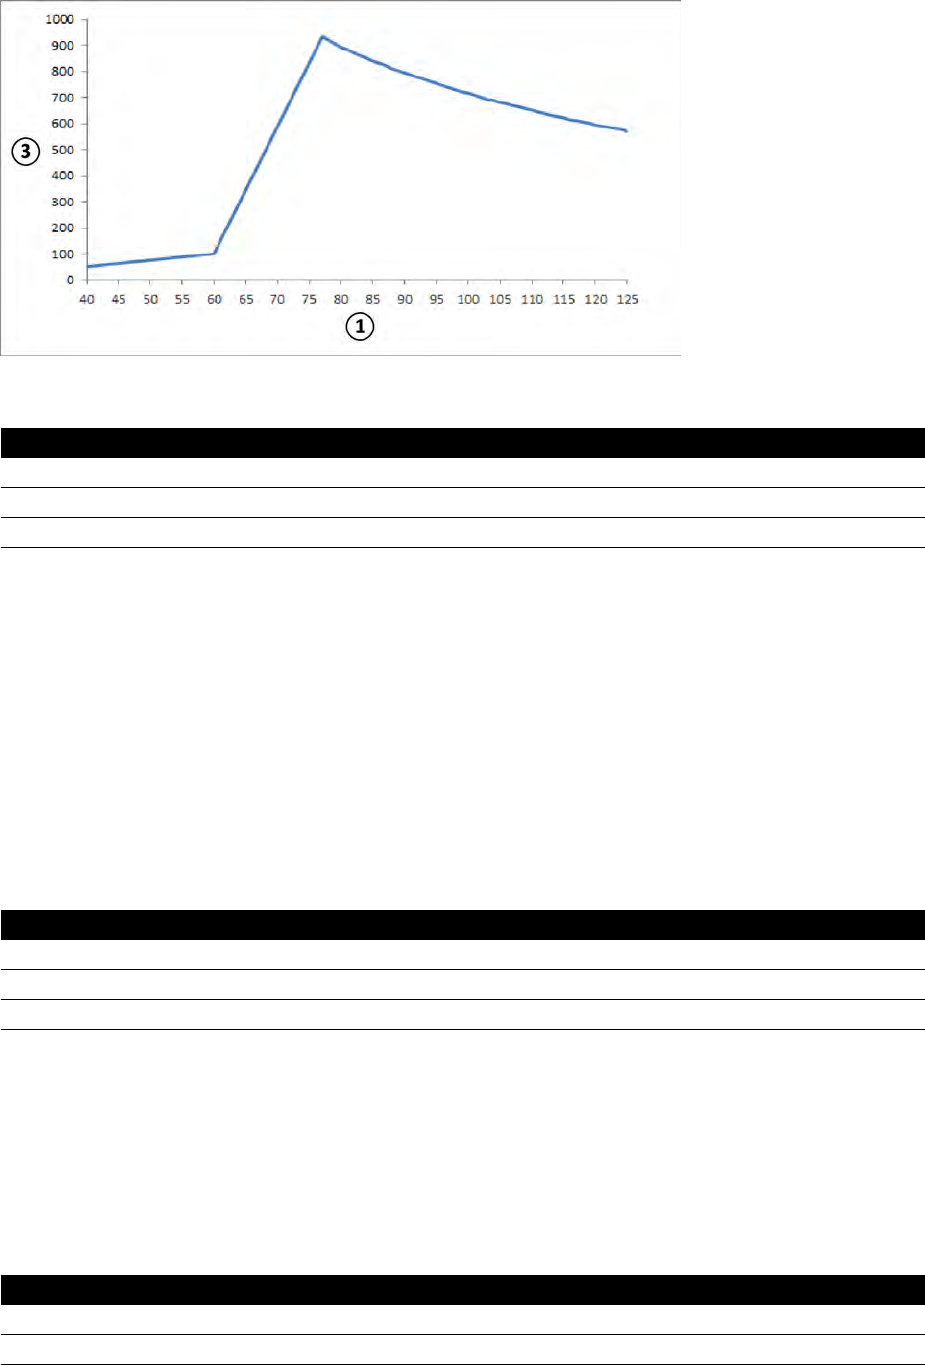

16.2.1 Moc wyjściowa lampy.......................................................................................... 270

16.2.2 Obciążenie systemu............................................................................................. 271

16.20 Typowe wartości referencyjnej kermy w powietrzu (moc)...................................................297

16.20.1 Systemy C12/F12..................................................................................................298

16.20.2 Systemy F15......................................................................................................... 300

16.20.3 Systemy C20/F20..................................................................................................302